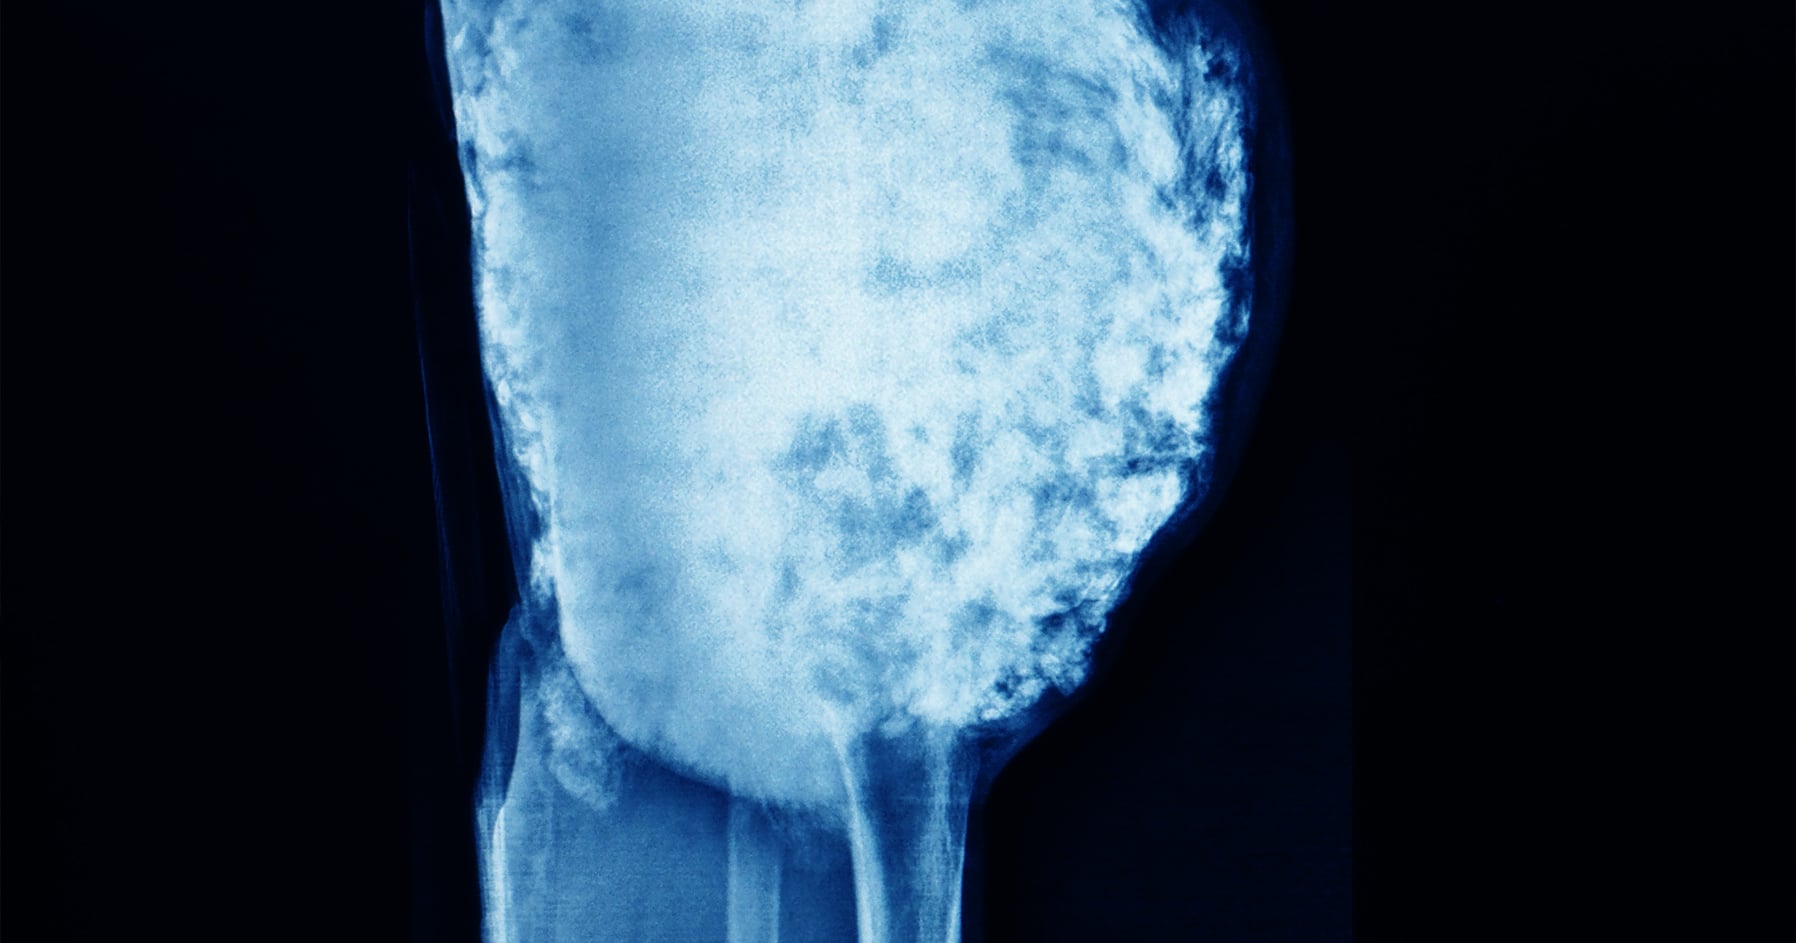

Image of bone tissue in the body.

Osteosarcoma is a rare cancer and is the most common type of cancer that arises in bones, distinguished by the production of unhealthy or immature bone by malignant cells. It most commonly develops in long bones like the femur (thigh), and its origin is still not clear to this day. It is usually found at the end of long bones.

Local (the affected bone) pain is the most common symptoms reported by patients. The doctor may feel a mass or tumor that is usually tender to touch. There is usually no fever, chills, malaise or weight loss. A plain radiograph of the affected area commonly shows a very distinctive pattern. Some blood tests specific to bone might help in the diagnosis.